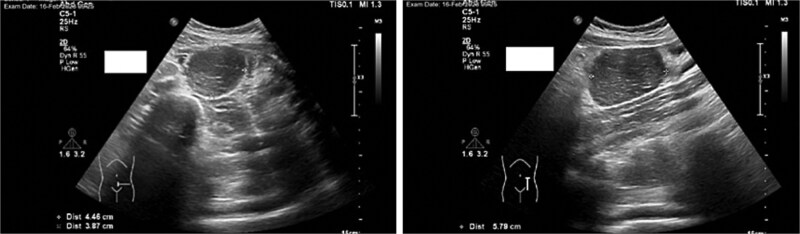

Castleman病是一种罕见的淋巴细胞增生性疾病,病因不明,其最常见的症状是纵隔淋巴结肿物。虽然它在年轻人中很少见,但在成年人中很普遍。我们报告一个病例14岁的男孩谁是入院的外科急性右侧腹痛,怀疑急性阑尾炎。术前腹部影像学检查显示炎性阑尾及大肠系膜肿块。经组织病理学检查证实为急性阑尾炎及单中心肠系膜肿块,经腹腔镜手术切除。

The most prevalent symptom of Castleman disease, a rare lymphoproliferative condition with an unclear etiology, is a mediastinal nodal mass. While it is quite uncommon in youngsters, it is prevalent in adults. We report a case of a 14-year-old boy who was admitted to the department of surgery for acute right-sided abdominal pain, with suspected acute appendicitis. Preoperative imaging investigation of the abdomen showed an inflammatory appendix as well a large mesenteric mass. Histopathology examination confirmed the diagnosis of acute appendicitis and mesenteric mass unicentric Castleman after resection by laparoscopic approach.